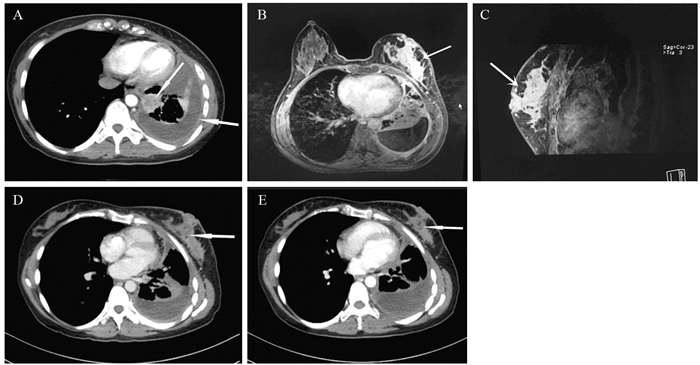

在ST-PACS医学图像工作站(北京思创贯宇科技开发有限公司)上选取肿瘤最大层面相邻的三个层面,利用自由形标记工具在ADC图上手工绘制ROI,在b=1 000s/mm2下测量平均ADC值(ADCmean)、最小ADC值(ADCmin),每个层面测量3次,并计算平均值。相对ADC值(rADC)=瘤体区ADC值/对侧脑白质ADC值,见图 1。

![]() 图 1 少突胶质细胞瘤(WHOⅢ级;IDH-1突变/1p19q共缺失)MRI和病理学表现Figure 1 MRI and pathological manifestations of oligodendrocytoma (WHO gradeⅢ) with IDH-1 mutation/1p19q co-deletionA, B: the lesions in the right temporal-parietal lobe showed heterogeneous low signal and high signal on T1WI and T2WI, respectively; C, D: DWI presented as an inhomogeneous equal-slightly higher signal (mild diffusion restricted) (C) and ADC map showed an inhomogeneous low-slightly higher signal (D); E: the measurement method of ADC value to select three ROI (10-20 mm2) in lesions and take their average values as well as select the contralateral normal brain white matter to calculate rADC; F: tumor cells were arranged in diffuse pieces, the nucleus with obvious atypia was large, and numerous necrotic regions were found in the lesions (HE ×200).

图 1 少突胶质细胞瘤(WHOⅢ级;IDH-1突变/1p19q共缺失)MRI和病理学表现Figure 1 MRI and pathological manifestations of oligodendrocytoma (WHO gradeⅢ) with IDH-1 mutation/1p19q co-deletionA, B: the lesions in the right temporal-parietal lobe showed heterogeneous low signal and high signal on T1WI and T2WI, respectively; C, D: DWI presented as an inhomogeneous equal-slightly higher signal (mild diffusion restricted) (C) and ADC map showed an inhomogeneous low-slightly higher signal (D); E: the measurement method of ADC value to select three ROI (10-20 mm2) in lesions and take their average values as well as select the contralateral normal brain white matter to calculate rADC; F: tumor cells were arranged in diffuse pieces, the nucleus with obvious atypia was large, and numerous necrotic regions were found in the lesions (HE ×200).1.4 统计学方法